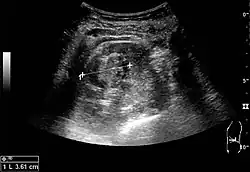

On renal ultrasonography, a solid renal mass appears in the US exam with internal echoes, without the well-defined, smooth walls seen in cysts, often with Doppler signal, and is frequently malignant or has a high malignant potential. The most common malignant renal parenchymal tumor is renal cell carcinoma (RCC), which accounts for 86% of the malignancies in the kidney. RCCs are typically isoechoic and peripherally located in the parenchyma, but can be both hypo- and hyper-echoic and are found centrally in medulla or sinus. The lesions can be multifocal and have cystic elements due to necrosis, calcifications and be multifocal (Figure 8 and Figure 9). RCC is associated with von Hippel–Lindau disease, and with tuberous sclerosis, and US has been recommended as a tool for assessment and follow-up of renal masses in these patients.[3]